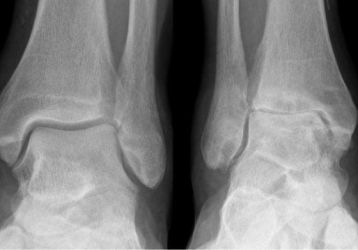

Народные средства в терапии остеоартроза голеностопного сустава: рецепты мазей, растирок, компрессов

Народные средства в терапии остеоартроза голеностопного сустава: что работает лучше всего? Можно ли лечиться без врачей? Рецепты и ингредиенты мазей, настоек, компрессов.